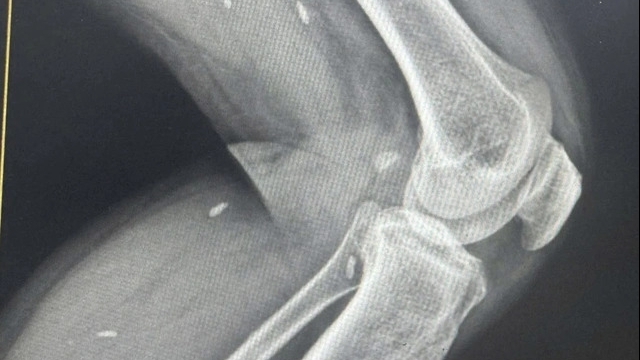

| Thăm khám cho bệnh nhân điều trị tại Bệnh viện Việt Đức. |